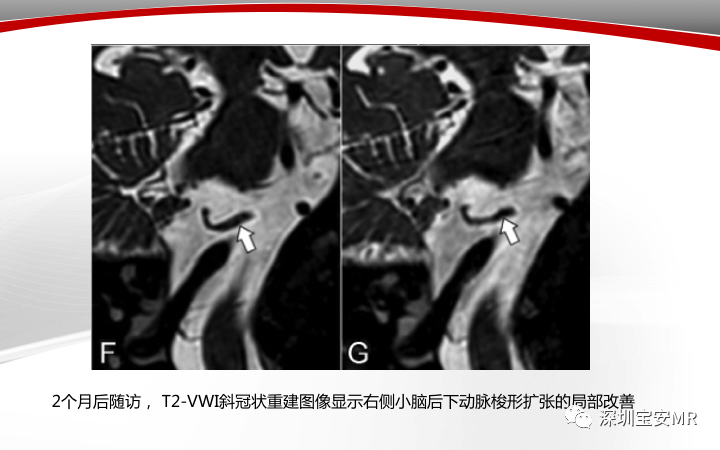

【病例】小脑后下动脉夹层1例MR